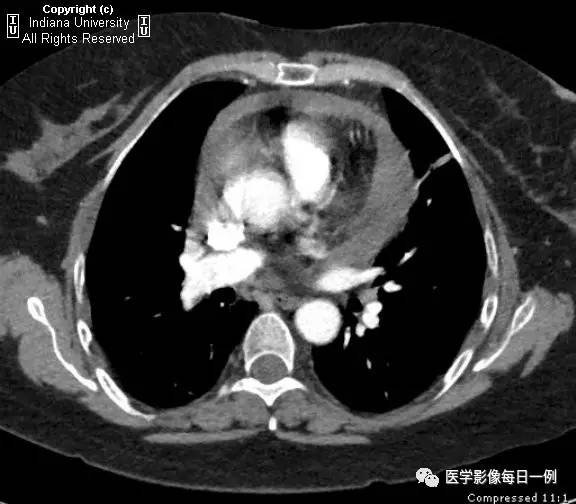

【影像学表现】胸片示心脏较前明显增大,无局部浸润。CT示心脏周围液体,厚度超过2cm,与水呈等密度。无胸腔积液。 医学百科网 | YxBaike.Com

心包积液

【诊断】类风湿性关节炎继发心包积液 医学百科网 | YxBaike.Com

【要点】-心包积液 医学百科网 | YxBaike.Com

- 最好的诊断线索是在连续的X片上心脏大小的改变。

- 通常心包液体为15-50毫升。

- 超声心动图是最好的成像工具,CT对病变特征显示最佳。